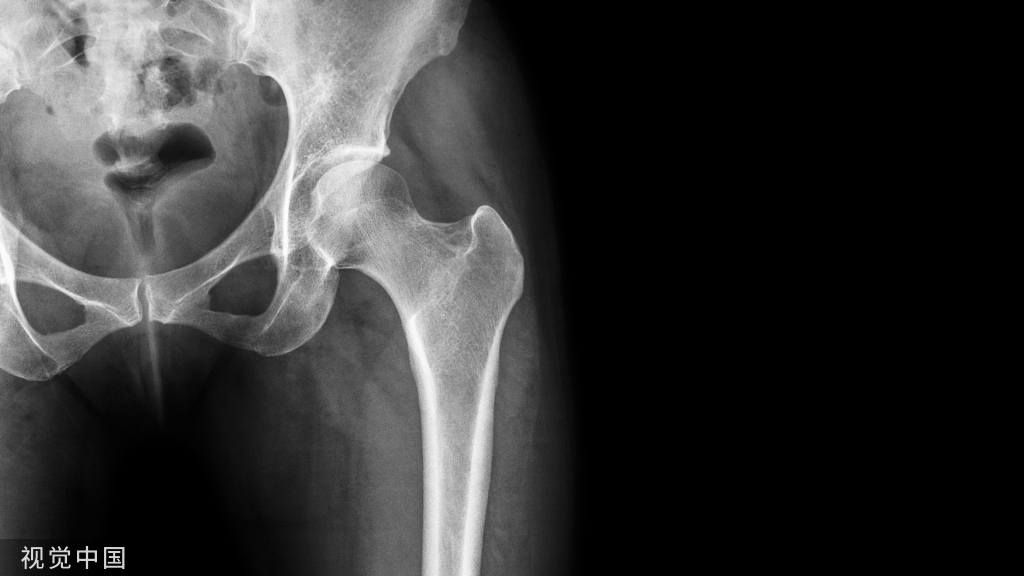

过伸型胫骨平台骨折的治疗,超详细解析!